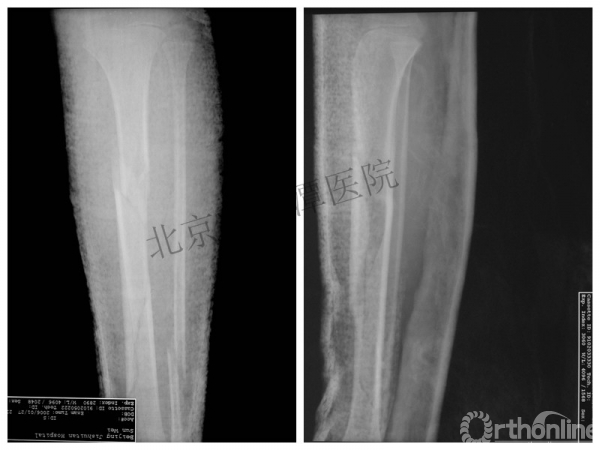

男孩、9岁,滑雪受伤,胫腓骨螺旋形骨折(粉碎性)

手法整复,石膏制动!

整复后7天

儿童具备强大的愈合潜力,同样也有极强的塑形能力